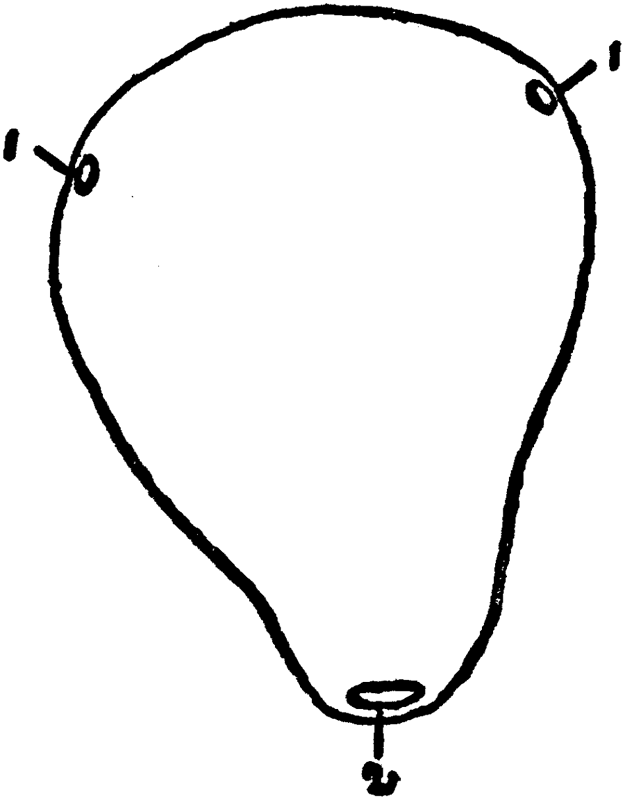

1. Openings into the Fallopian Tubes. 2. Mouth of the Womb.

The Fallopian Tubes. The Fallopian tubes (so called from Fallopius, a great anatomist, who discovered them; also called oviducts: egg conductors, because they conduct the eggs from the ovary into the uterus) are two very thin tubes, extending one from each upper angle of the womb to the ovaries; but at their ovarian end they expand into a fringed and trumpet-shaped extremity. The fringes are referred to as fimbria. They are about five inches long and only about one-sixteenth of an inch in diameter; the function of the tubes is to catch the ova as they burst forth from the ovaries and to convey them to the uterus. Taking into consideration the very narrow lumen, or caliber, of the Fallopian tubes, it is easy to understand why even a very slight inflammation is apt to clog them up, to seal their mouths or openings, thus rendering the woman sterile, or incapable of having children. For, if the Fallopian [36]tubes are "clogged" up, the eggs, or ova, have no way of reaching the uterus.

The Greek name for the Fallopian tube is salpinx (salpinx in Greek means tube). An inflammation of the Fallopian tube is therefore called salpingitis. (A salpingitis has the same effect in causing sterility in the female as has an epididymitis in the male.) Salpingectomy is the cutting away of the whole or of a piece of the Fallopian tube (corresponds to vasectomy in the male).

The Uterus. The uterus or womb is the organ in which the fertilized ovum, or egg, grows and develops into a child. It is a hollow muscular organ, about the size of a pear, with thick walls, capable under the influence of pregnancy of great expansion and growth. The broad part of the pear is called the body of the uterus; the lower narrow part is called the neck of the uterus, or cervix. The uterus in the adult girl or woman is about three inches long, two inches broad in its upper part and nearly an inch thick. It weighs from an ounce to an ounce and a half. When the uterus is in a pregnant condition, it increases enormously, both in size and in weight, as we will see in a future chapter. The cavity of the uterus is somewhat triangular in shape; at each upper angle is the small opening communicating with the Fallopian tube; the upper portion of [37]the uterus is called the fundus; the external opening of the womb, situated in the center of the cervix, is called the mouth of the womb, or the os, or external os.